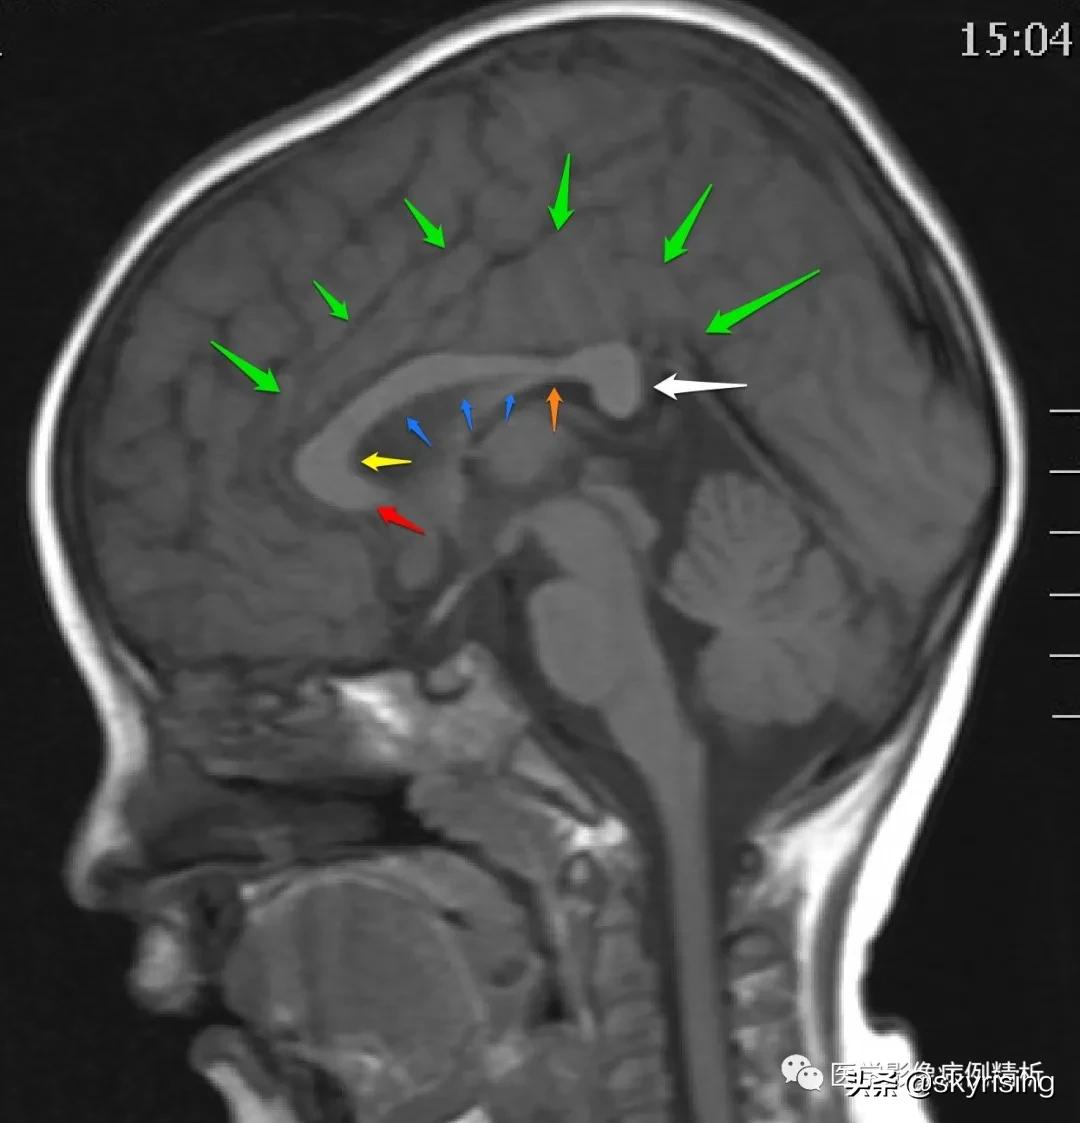

T1WI矢状位:红色箭头所示胼胝体嘴部、膝部、体前部缺如,正常扣带沟形态消失,双侧额叶延伸至侧脑室内。

下图为2岁婴儿脑矢状位T1WI图像,清晰显示完整的胼胝体,红色箭头为嘴部,黄色箭头为膝部,蓝色箭头为体部,白色箭头为压部,注意棕色箭头所示胼胝体体部后缘略变扁,是一种正常的变异现象,不是发育异常,非常常见。因小儿脑发育未完全,扫描角度有偏差,绿色箭头显示正常的扣带沟,基本形态存在,但不完全。注意与后图中示意图胼胝体及扣带回对比。

胼胝体是连接双侧大脑半球神经纤维的重要组织,主要包括嘴部、膝部、体部、压部如图所示,其矢状面周围主要由扣带回包围,绿色箭头所示为扣带回内翻形成的扣带沟,额顶叶受此结构阻挡无法延伸至胼胝体旁。

T1WI矢状位如下图所示,本例患者确诊为垂体柄阻断综合征并胼胝体缺如、垂体后叶异位。两图为相邻的矢状位正中图像,可以清晰显示缺如的胼胝体,如红色箭头所示区域,未能看到正常的扣带回内翻形成扣带沟,第三脑室上抬、侧脑室正常形态消失。绿色箭头为视交叉,黄色箭头结节状高信号为异位的垂体后叶,白色箭头所示为垂体前叶,正常鞍区后方的垂体后叶上移至黄色箭头区域。